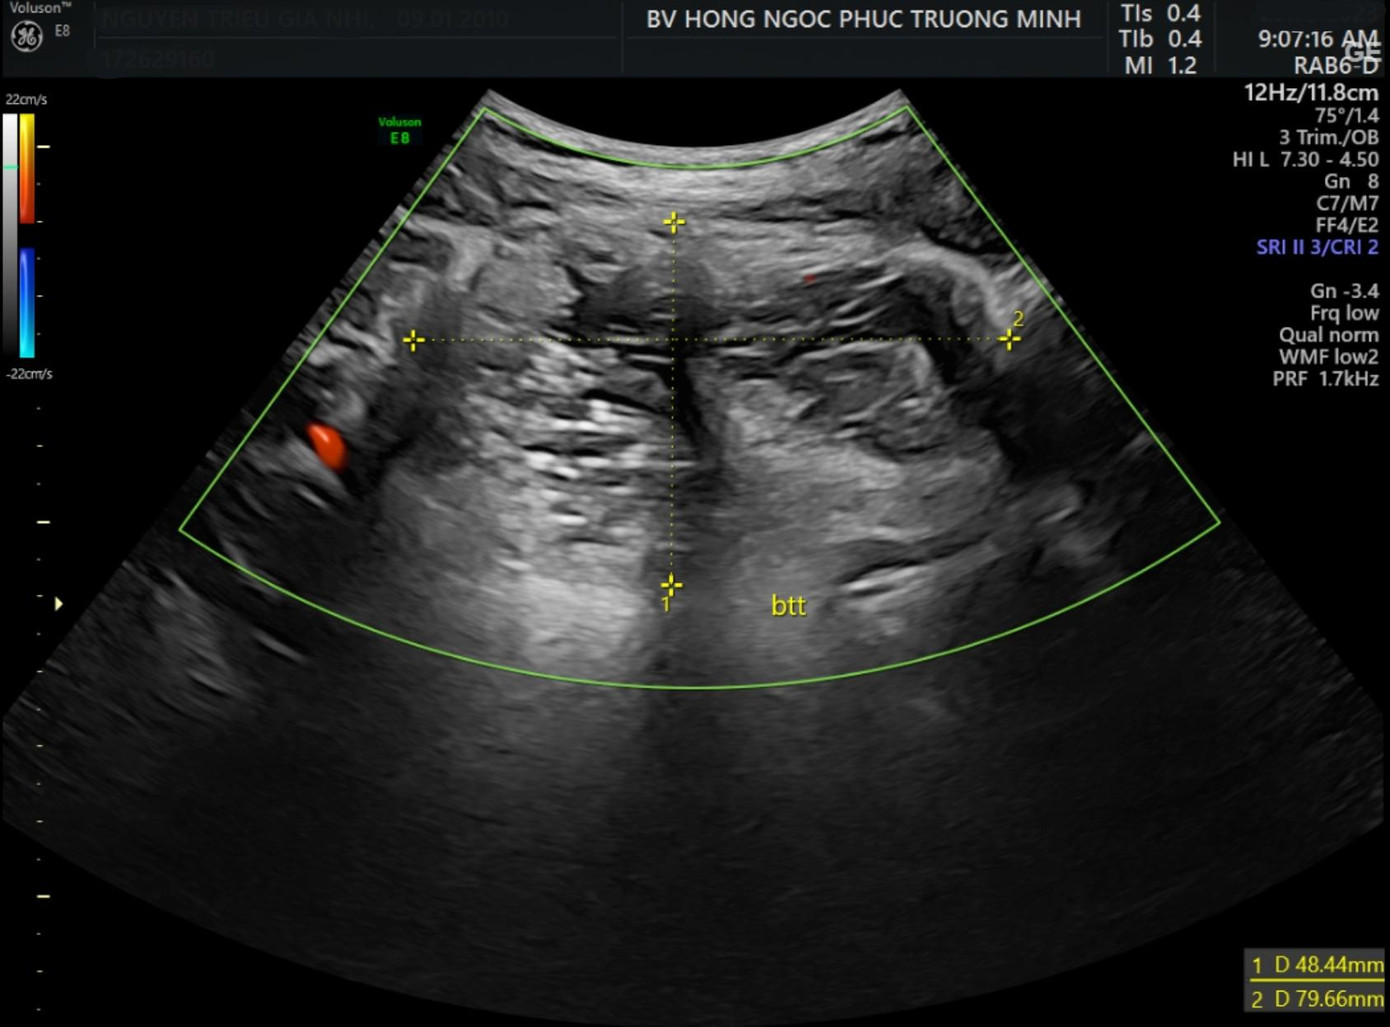

Sau khi nhập viện, các bác sĩ đã nhanh chóng kiểm tra, đánh giá tình trạng bệnh lý cũng như hoàn thiện các chỉ định cận lâm sàng để xác định tính chất khối u và tìm phương án điều trị phù hợp. Hình ảnh trên máy siêu âm hiển thị 2 khối u nang nằm ở 2 bên buồng trứng, có kích thước lần lượt là 46x59mm và 48x80mm.

| Hình ảnh siêu âm cho thấy khối u kích thước 48*80mm tại buồng trứng trái. |